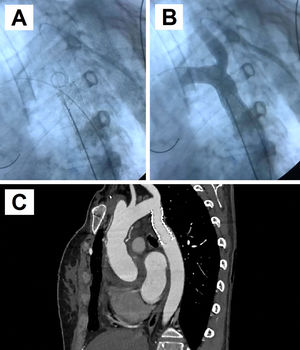

A) Corte coronal de la TC de aorta que confirmó el hallazgo de disección aguda de aorta tipo II de Bakey limitada a la raíz aórtica y aorta ascendente proximal, dilatada con un diámetro máximo de 65mm. B) Fotografía del campo quirúrgico objetivándose dilatación aislada de la raíz aórtica y aorta ascendente proximal. C) Fotografía del campo quirúrgico con sustitución de la raíz aórtica y aorta ascendente por un conducto aortovalvulado con prótesis mecánica y reimplante de ambos ostia coronarios sobre el conducto.

La paciente fue intervenida de sustitución de la raíz aórtica y aorta ascendente por un conducto aortovalvulado con prótesis mecánica y reimplante de ambos ostia coronarios sobre el conducto (fig. 1 B-C). El abordaje fue por esternotomía media. Se estableció circulación extracorpórea con canulación arterial en arteria axilar derecha subclavicular y canulación venosa en aurícula derecha. No requirió parada circulatoria ante la afectación limitada a aorta ascendente, estando la rotura intimal de la pared aórtica semicircunferencial a nivel de la unión sinotubular, extendiéndose hasta el ostium coronario izquierdo sin afectarlo, realizándose la intervención con pinzamiento aórtico y bajo hipotermia moderada. La evolución postoperatoria fue favorable desde el punto de vista hemodinámico, pero estuvo marcada por la situación respiratoria y neurológica. Requirió intubación prolongada y realización de traqueostomía ante hipoxemia y hallazgo de consolidación pulmonar en relación con posible broncoaspiración. Neurológicamente, lenta conexión con el medio sin respuesta a órdenes ni movilización de extremidades, con hallazgo en TC cerebral postoperatorio de múltiples infartos isquémicos agudos. No obstante, la situación fue mejorando progresivamente los días posteriores con recuperación neurológica completa y decanulación de traqueostomía, pudiendo ser alta hospitalaria al mes de la intervención.